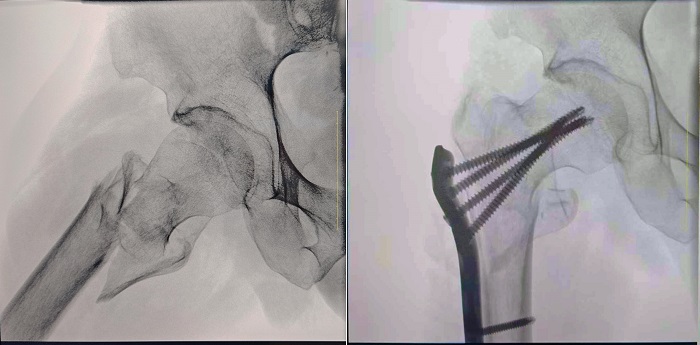

患者:70歲,男

臨床診斷:右股骨粗隆間骨折,伴有下肢位移、外旋

術(shù)式:右股骨粗隆間骨折切開復(fù)位內(nèi)固定術(shù)

一體式移動C型臂拍攝的術(shù)前影像

大視野 高清成像 觀察更全面

普愛醫(yī)療一體式移動C型臂采用30CM×30CM的平板探測器,能夠幫助醫(yī)生全面觀察患者斷端分離錯位情況,確保手術(shù)方案的精準(zhǔn)制定。